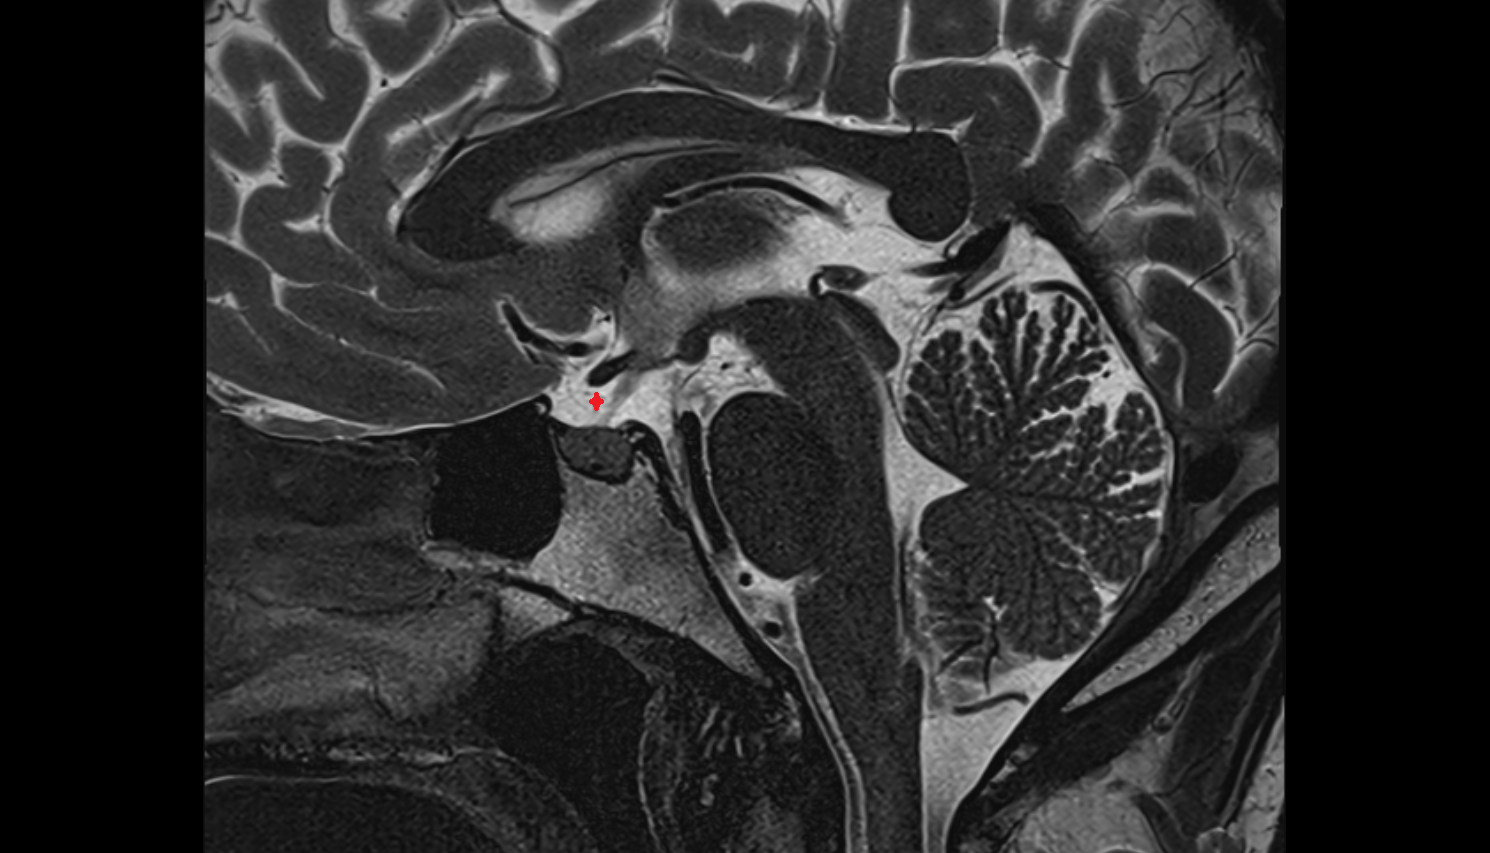

- Pituitary stalk

- Pituitary gland

- Anterior lobe of pituitary gland

- Posterior lobe pituitary gland

- Sella turcica